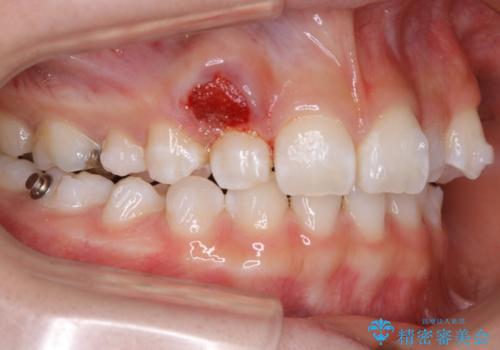

先天欠如

稀に、乳歯が抜けてもその後に永久歯が生えてこないことがあります。生まれつき歯の元となる「歯胚」というものが欠如していることが原因で本数が少なることを「先天欠如」といいます。

こういったケースの治療では欠損している歯の本数分反対の顎の歯(上顎に欠損がある場合は下顎の歯)を抜歯してスペースの調整をする場合や、欠損歯の幅分のIPRを反対の顎の歯に設定することでスペースのコントロールをするという方法、欠損している歯の分のスペースを残して矯正を終了し最後にブリッジ治療やインプラントで歯の本数を増やすという方法があり、状況や患者さんの希望により選択をしていきます。